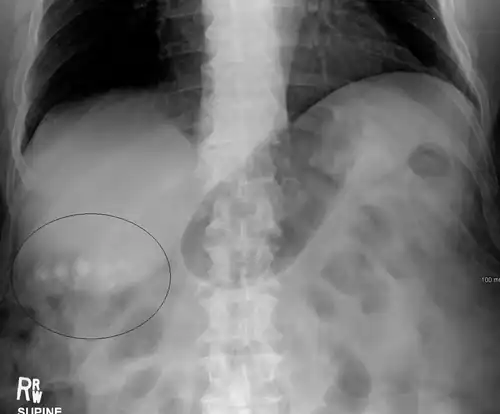

Gallstones as seen on plain X-ray